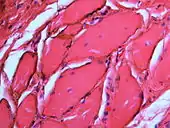

Over time, the amalgam particles embedded in the soft tissues corrode.[5]: 183 Macrophages take up the exogenous particles, and the silver in amalgam leads to staining of collagen fibers.[5]: 183

- Large particles may be surrounded by chronically inflamed fibrous tissue

- Smaller particles surrounded by more significant inflammation, which may be granulomatous or a mixture of lymphocytes and plasma cells